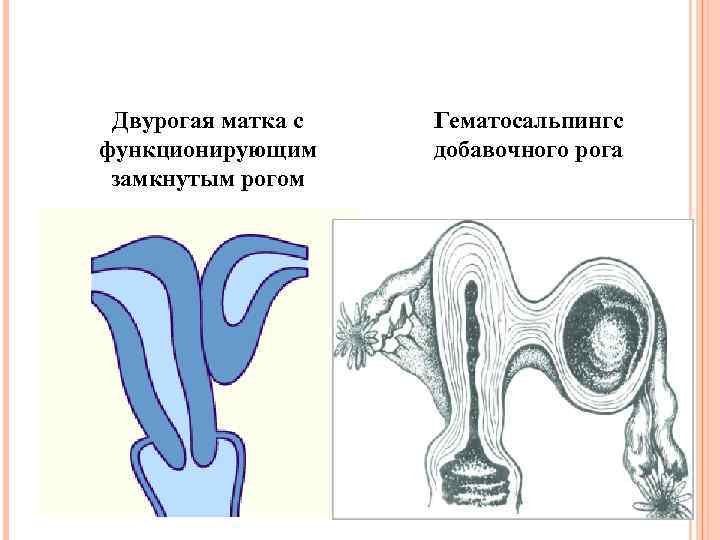

Двурогая матка с функционирующим замкнутым рогом Гематосальпингс добавочного рога

Двурогая матка с функционирующим замкнутым рогом Гематосальпингс добавочного рога